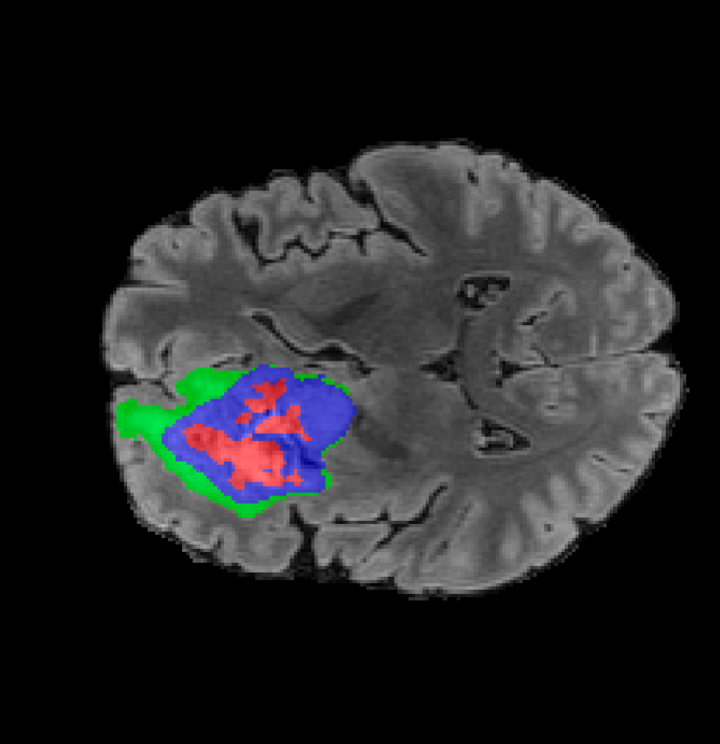

Tumour Information Preservation. For the brain tumor segmentation, we use a Swin UNETR model[27, 70], trained with random rotation, and intensity as data augmentation. In Figure 5, we highlight the tumor profiles of the generated MRIs compared to the ground truth tumour profile. In the test set with human ground-truth annotations (), the real MRI Dice score is 85.15 while the generated MRIs from a single slice have a dice score of 83.09. This shows how the generated MRIs indeed preserve the tumor information and can act as an affordable and informative pseudo-MRI, before conducting an actual costly MRI examination in hospitals.

B.4 Tumour Information Preservation

On the test set with human ground-truth annotations (), the brain volumes generated from single slice input preserve the volume of the different tumour components (paired t-test, for all 3 classes) (see Table 3). The real MRI Dice scores are put for reference to our generated MRIs. X-Diffusion outperforms baselines TPDM [36] and ScoreMRI [18] in tumour preservation (see Table 3 and Figure 12). We ran experiments comparing the tumour segmentation Dice Score varying X-Diffusion configurations. The multi-slice input X-Diffusion achieves a marginally better Dice Score than the single-slice input model (83.47 83.09). We also ran experiments with slice input used for volume reconstruction intersecting or not with tumour. We observe on average a drop of 6% Dice Score (see Table 3). Further away from the tumour the input slice for volume reconstruction is selected, and we observe a linear decrease in tumour segmentation Dice Score with the lowest value of 77.21 Dice Score (see Figure 15).

| Test Dice Score | |||||

|---|---|---|---|---|---|

| X-Diffusion Generated MRIs | ET | WT | TC | Average Dice | 3D PSNR(dB) |

| single slice | 75.48 | 89.24 | 84.57 | 83.09 | 35.81 |

| multi-slice | 75.82 | 89.56 | 85.04 | 83.47 | 36.13 |

| multi-slice (only-tumour) | 76.12 | 90.04 | 85.87 | 84.01 | 36.98 |

| multi-slice (no-tumour) | 70.14 | 84.29 | 81.65 | 78.69 | 33.24 |

| Real | 76.47 | 91.13 | 86.24 | 85.15 | N/A |